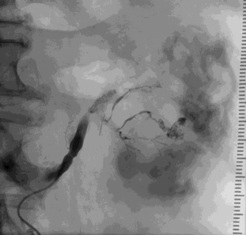

腹腔 动脉造影发现造影剂外溢,但供血动脉似乎来自于胃十二指肠动脉,但不确定 |

超选择胃十二指肠动脉显示出血的动脉来自于胃十二指肠动脉的一个细小的未命名动脉分支 |

弹簧栓子阻塞胃十二指肠动脉后造影 |

选择性胰背动脉造影未发现明显出血 |